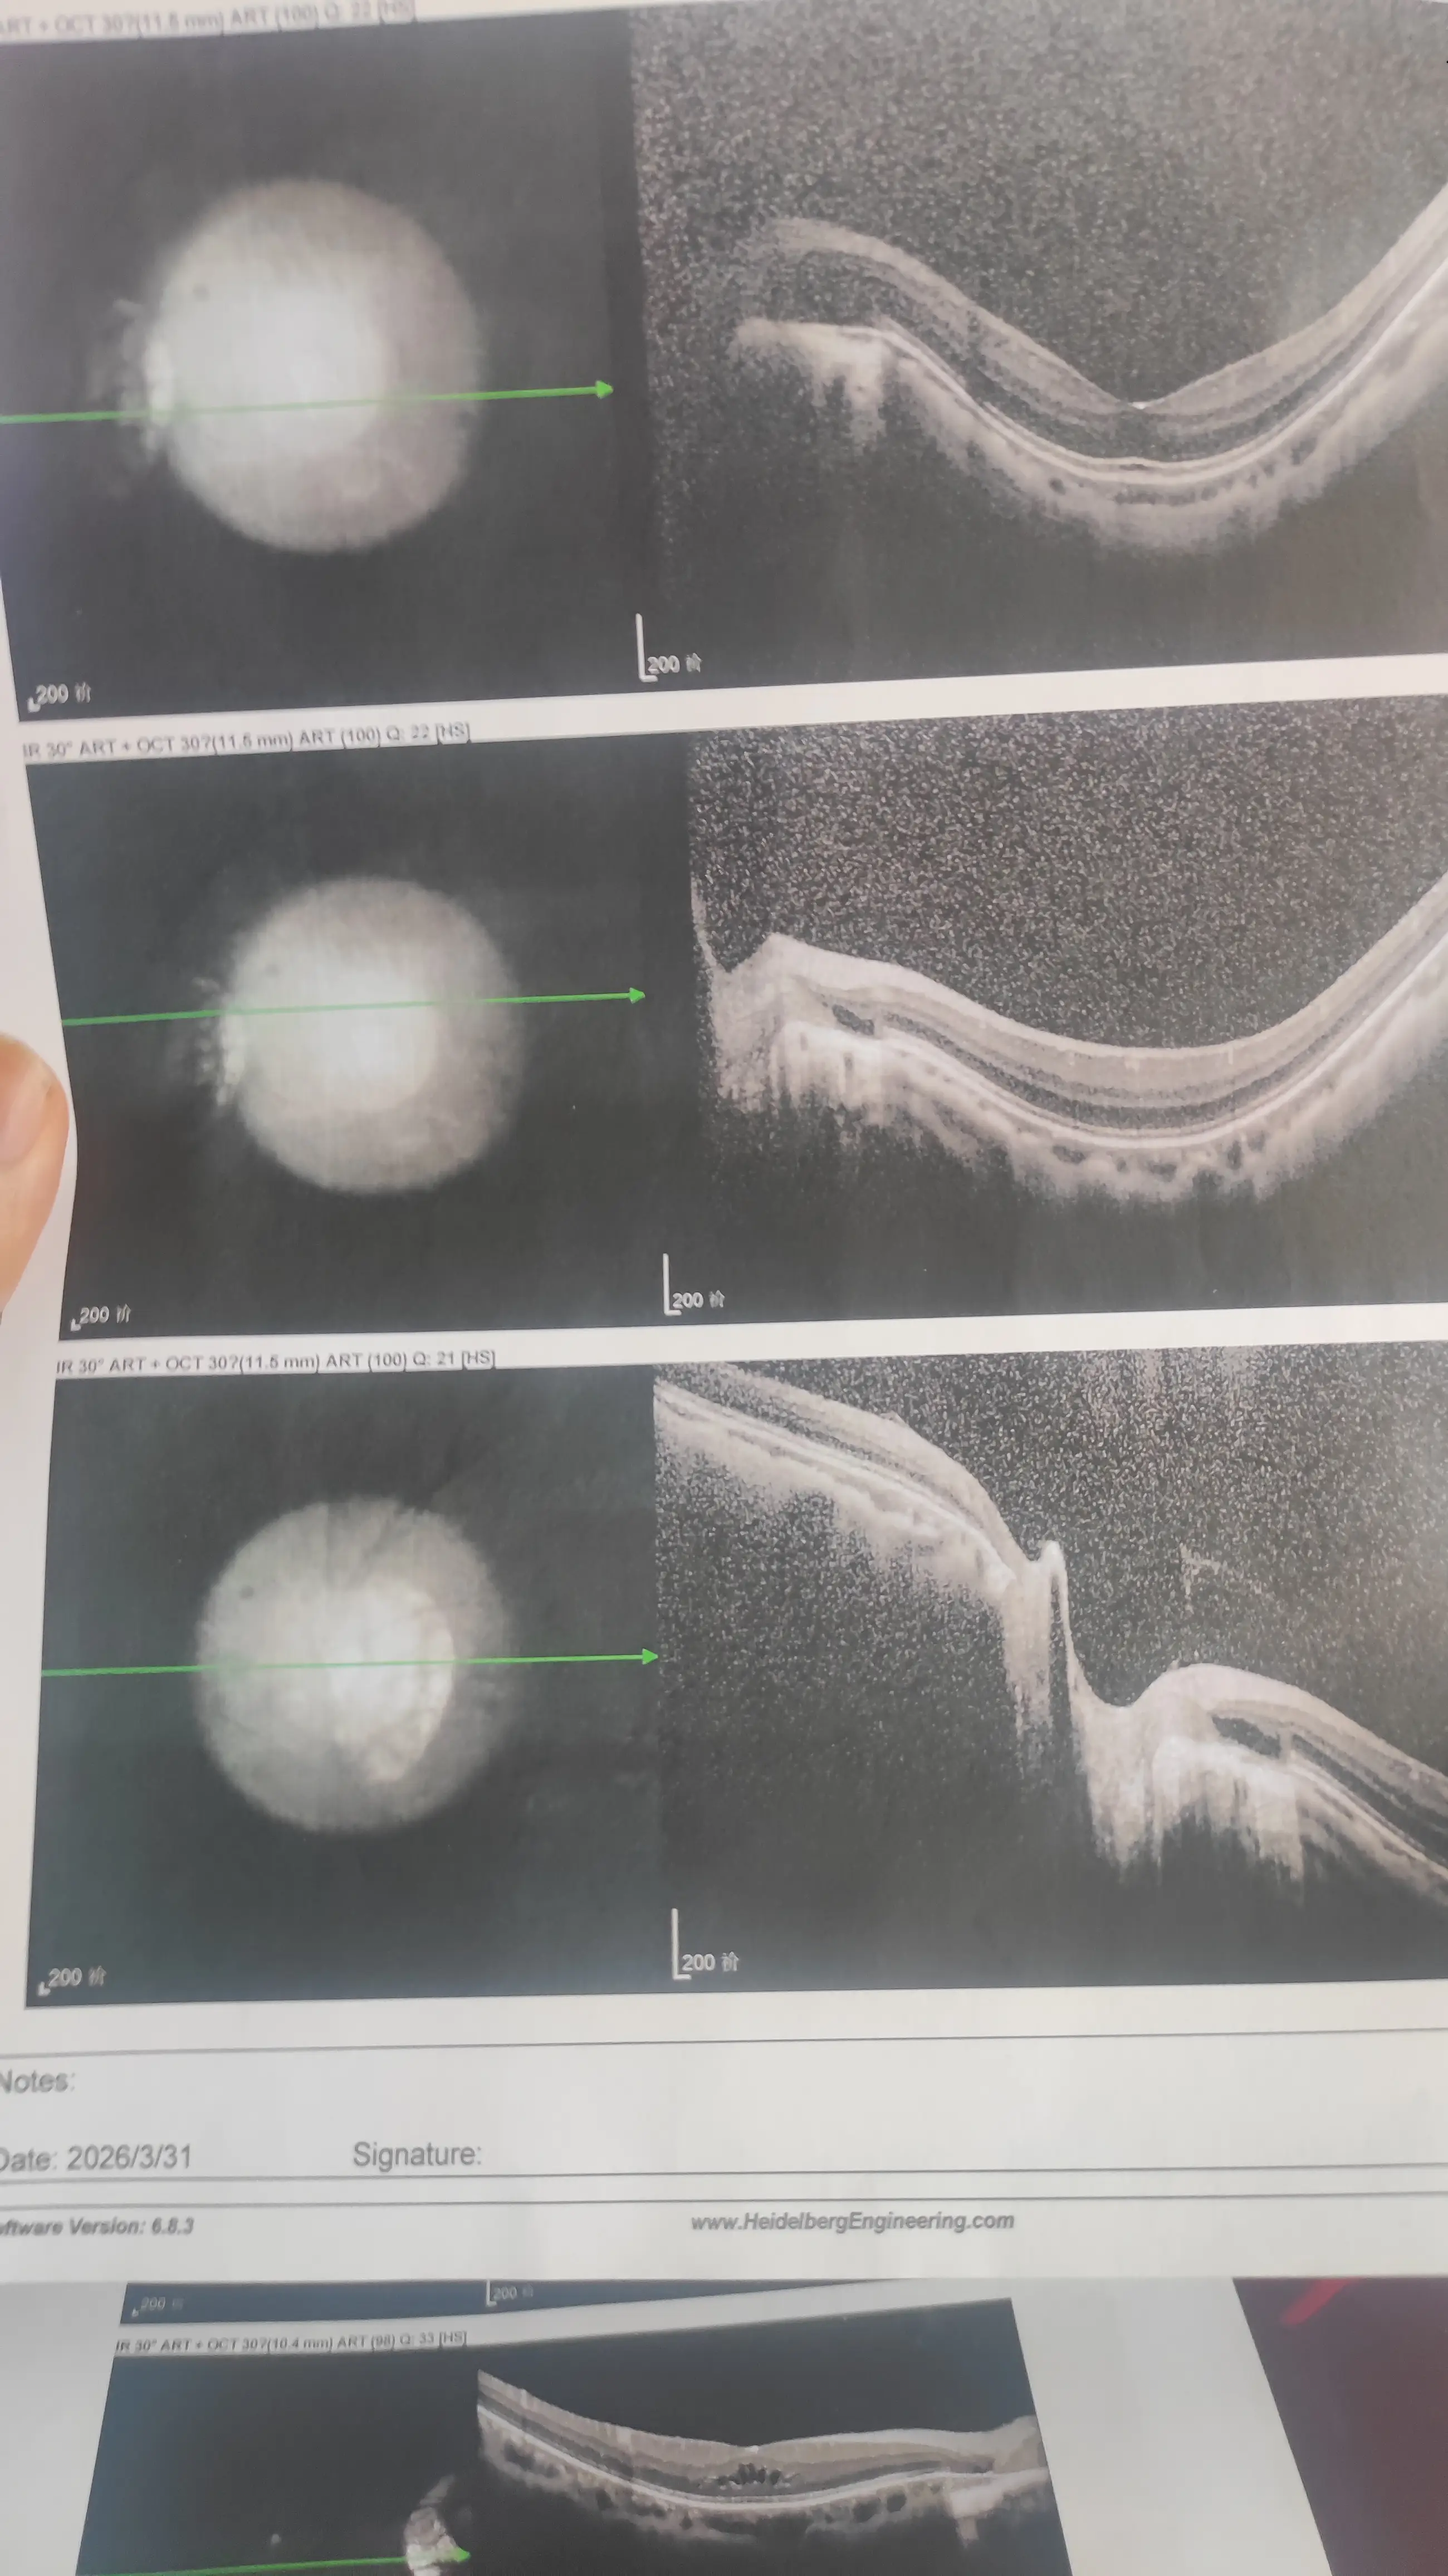

然后就喜提了一个坏消息:视网膜脱落。

希望你们都能好好的,如果有和站长一样,高度近视的,一定要定期去医院检查一下眼底。

提前发现的话,不仅治疗简单,花费也少。

最后,给大家看一下病例吧,以示警戒,希望大家关爱用眼健康!